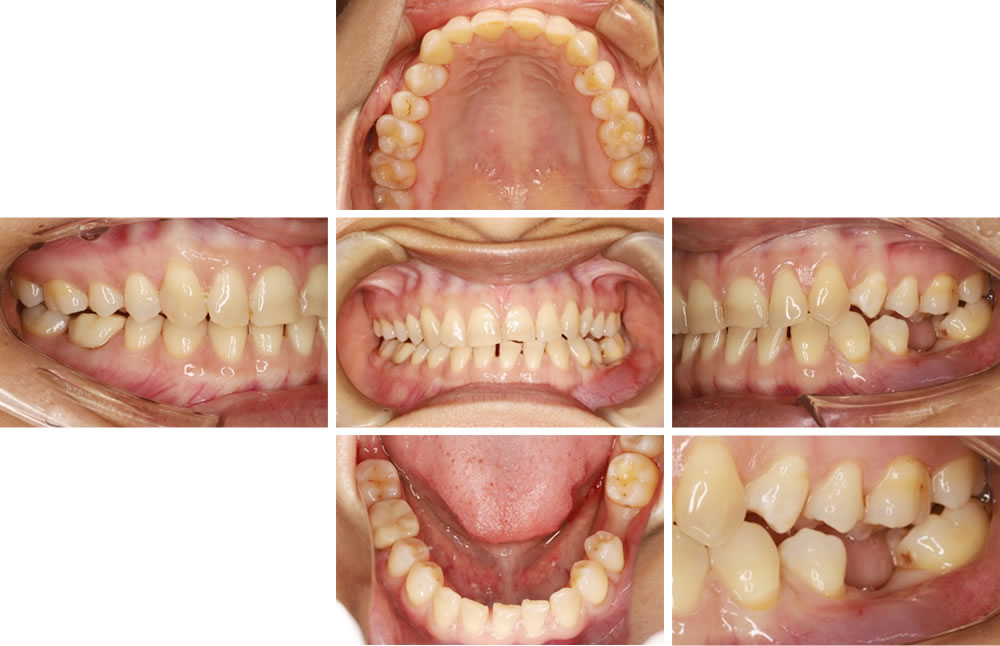

③他院で抜歯した部分をインプラントで治療した症例

こちらの患者さまは他院でむし歯だったところを抜歯し、インプラント治療ができないと診断されたので当院で診てほしいという主訴で来院されました。患者さまと相談し、入れ歯にはしたくないとのことでしたので、インプラントで噛み合わせを回復する計画を立てました。

パノラマレントゲンにて診断後、インプラント埋入用のステント(インプラントの方向性や埋入深度を決めるためのマウスピース)を作成しました。その後、ステントを口腔内に入れてCTを撮影し、十分な骨の厚みを確認した後に埋入方向を決定しました。

インプラント手術の実施

ステントを使用して計画通りの位置にインプラントを埋入しました。その後、2ヵ月の治癒期間を経て、当該歯の最終的な上部構造(被せ物)の型取り・作成を行いセメントにて仮固定しました。(当院はもしもの状況に備えるため、基本的に仮固定しておりますが普段の生活で脱離してしまうことはほとんどございません。)

インプラント治療前後の比較

審美的・機能的共に改善し、患者さまにも大変ご満足いただけました。現在は3ヵ月のメンテナンスで良好な経過を追っています。

| 年齢・性別 | 30代女性 |

|---|---|

| 治療期間 | 3ヵ月/6回 |

| 治療費(税込) | 440,000円 (※治療費等の変更により現在の費用と異なる場合があります) |

| リスク・注意点 | ・メンテナンスの仕方次第でインプラント周囲炎になる可能性があります。 ・咬合力によってインプラント体が破折する可能性があります。・骨量によっては骨を作る処置が必要になったり、治療自体ができない場合があります。 ・糖尿病など、全身状態によっては治療が受けられない場合があります。 |